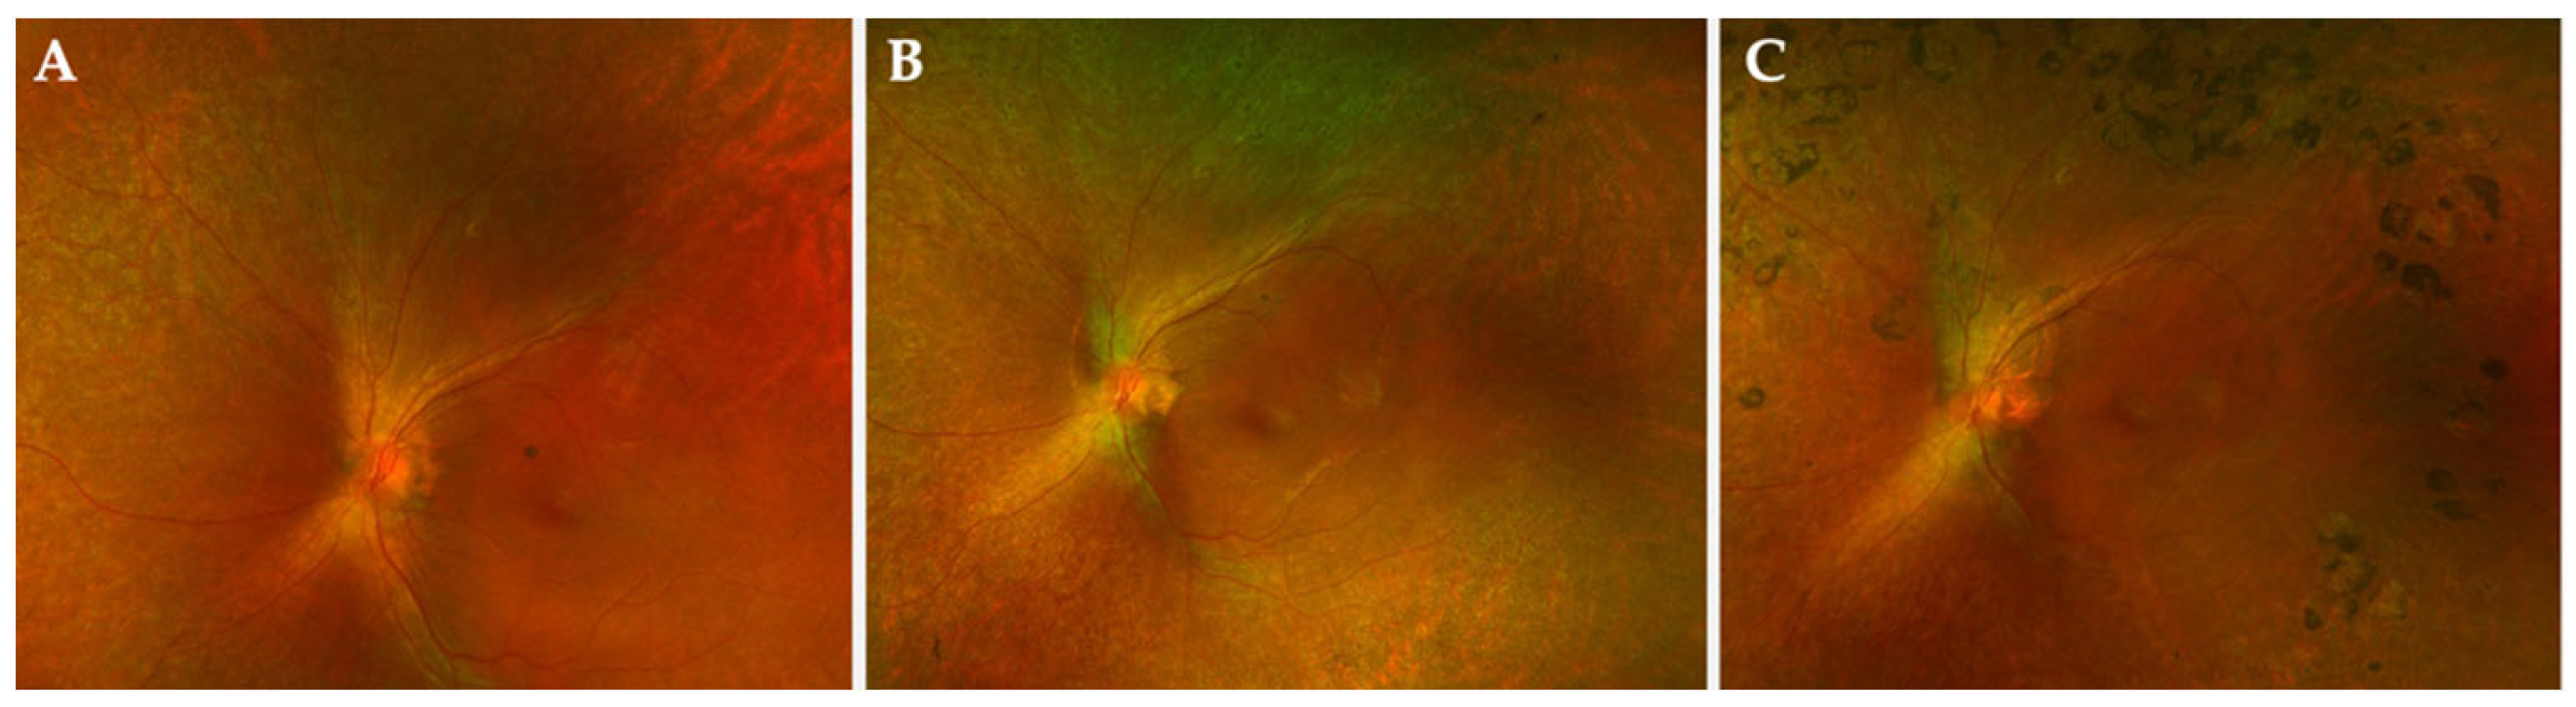

Surgical Technique